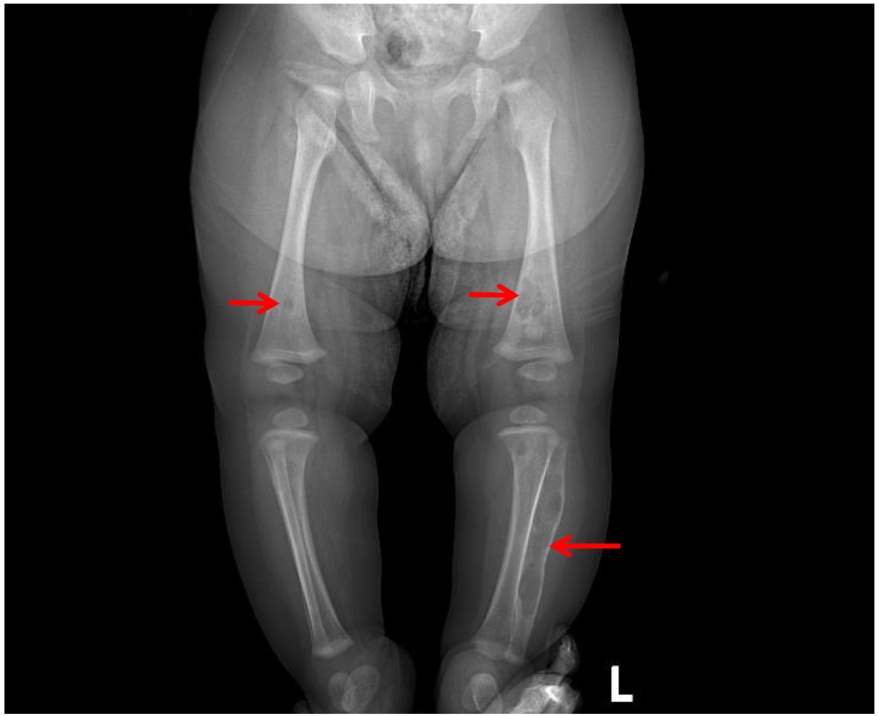

(4) 辅助检查:2025-09-07胸部X线:考虑双肺少许炎症;2025-09-08尿培养:铜绿假单胞菌,头孢他啶2S;2025-09-09血常规 + CRP复查:C反应蛋白30.88 (mg/L)↑,白细胞计数7.63 (×10^9/L) ,中性粒细胞百分率35.10↓,淋巴细胞百分比52.30%↑,淋巴细胞绝对值3.99 (×10^9/L)↑,血红蛋白88 (g/L)↓,血小板计数407 (×10^9/L)↑,血沉49.00↑,白介素644.55 pg/mL:2025-09-09免疫全套:免疫球蛋白IgG 3.48 g/L↓,免疫球蛋白IgGM 0.50 g/L,免疫球蛋白IgA 0.05 g/L↓,补体C3 1.69 g/L↑,补体C4 0.33 g/L;碱性磷酸酶:305.3U/L↑;2025-09-09左侧髋关节及左侧膝关节彩超:未见明显异常;2025-09-09胫腓骨正侧位X线(如图1):左腓骨形态略膨隆,髓腔内见长节段低密度区,边界不清,骨皮质膨胀、变薄,层状骨膜反应,邻近软组织肿胀。

Figure 1. Left tibia fibula AP & LAT X-ray

1. 左侧胫腓骨正侧位片

左腓骨形态略膨隆,髓腔内见长节段低密度区,边界不清,骨皮质膨胀、变薄,层状骨膜反应,邻近软组织肿胀。

患儿入院时外院已明确存在泌尿道感染及肺部感染,入院后继续予以头孢他啶(9.09~9.16)、万古霉素(9.10~9.16)抗感染治疗,患儿左下肢肿胀及活动情况较前好转,考虑骨髓炎可能,但患儿仍有反复低热,9.16患儿发热热峰升高,咳嗽较前明显,完善上呼吸道六项病原核酸,提示呼吸道合胞鼻病毒感染,停用抗生素,9.16~9.17予以丙种球蛋白调节免疫、雾化等治疗,患儿体温、咳嗽好转,结合患儿全身多处骨关节影像学表现,考虑诊断婴儿骨皮质增生症,9.17~9.18予以甲泼尼龙控制炎症反应,患儿体温降至正常,9.21患儿再次出现低热,于9.23开始规律口服醋酸泼尼松片并逐渐减量至10.4停药,患儿至今未再发热(如图6)。1月后复查,炎症指标大致正常,X线可见右侧胫骨低密度影恢复正常,左侧股骨下段、右侧股骨下段、左胫腓骨内部见多发骨质密度减低区,左腓骨髓腔不规则长段囊腔样扩大、皮质变薄、层状骨膜恢复(如图7)。4月后复查,炎症指标完全正常,X线双侧股骨下段、左胫腓骨内部见多发骨质密度减低区较前明显减少,合并左腓骨畸形膨大较前明显改善,符合婴儿型骨皮质增生症(如图8)。

Figure 7. Dual lower extremities X-ray

7. 双下肢X线

左侧股骨下段、右侧股骨下段、左胫腓骨内部见多发骨质密度减低区,左腓骨髓腔不规则长段囊腔样扩大、皮质变薄、层状骨膜恢复。

Figure 8. Dual lower extremities X-ray

8. 双下肢X线

双侧股骨下段、左胫腓骨内部见多发骨质密度减低区较前明显减少,合并左腓骨畸形膨大较前明显改善